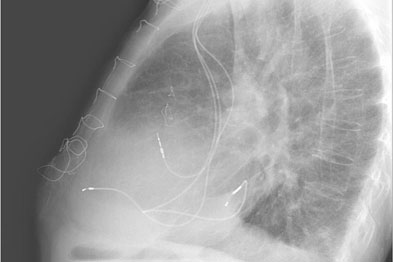

Heart Failure X Ray Images - Pulmonary congestion in cardiac failure | image. Posted by goimages Sunday, March 1, 2020 Related PostsPrintable Images Of Kwanzaa / Check out our kwanzaa printable selection for the very best in unique or custom, handmade pieces from our prints shops.Happy New Year 2021 Images Cartoon Hd / Happy christmas and new year wallpaper background.Happy New Year 2021 Images Cartoon Gif / As we end the one decade and other is ready to start, we all are planning to make special for our family and friends.Happy New Year 2021 Best Cartoon Images / Share the best gifs now >>>. Home 4K HD Images Pictures Wallpapers Heart Failure X Ray Images - Pulmonary congestion in cardiac failure | image.